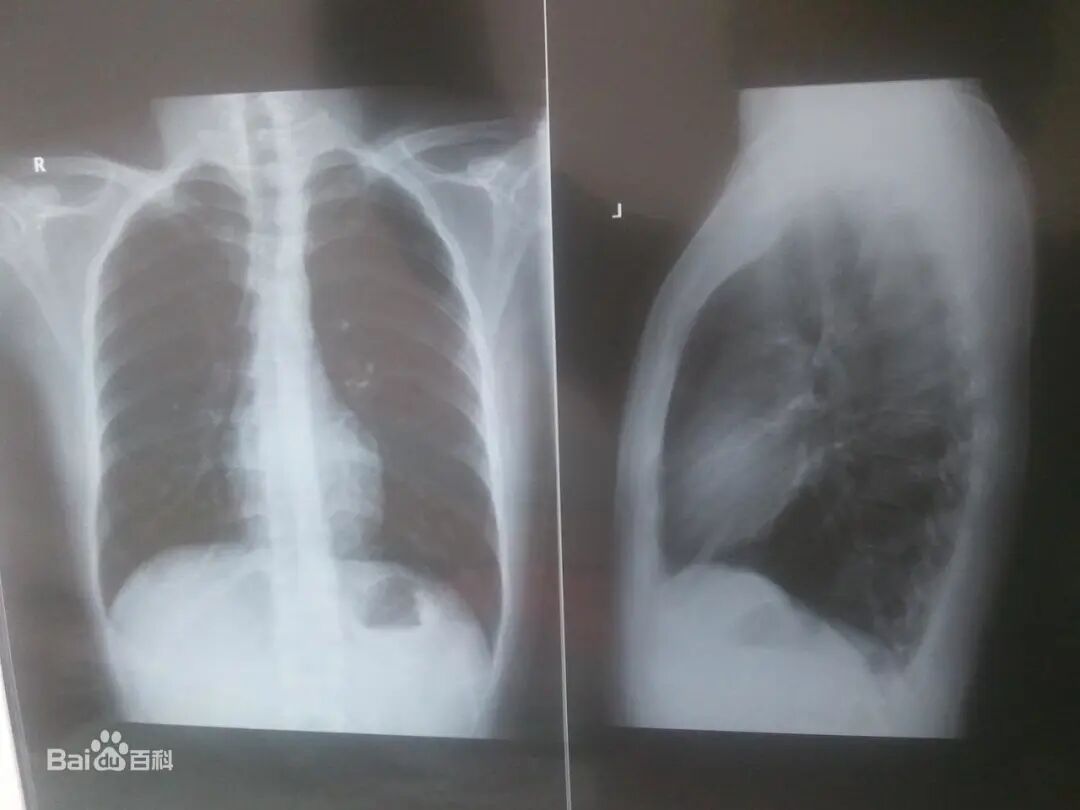

而我们在检查身体时,做的X光检查,比如胸透,也是利用X射线穿透力强的特点,来给身体里的器官来拍照的。

x光机为什么为什么要用x光来找毒蛇呢?本周孩子们好奇的问题还有…【把世界讲给孩子听】_https://www.jmylbn.com_新闻资讯_第2张

胸透影像

图片来源:百度百科